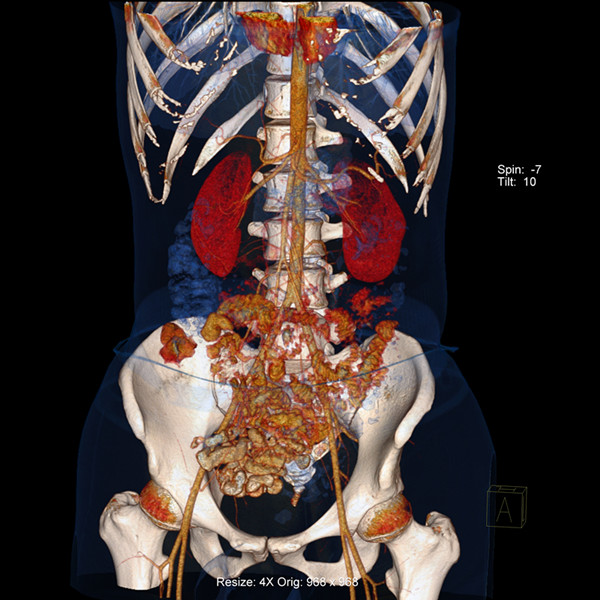

炫速雙源CT是目前世界上最先進的CT設(shè)備之一。它采用兩套64排圖像采集系統(tǒng),結(jié)合“飛焦點”技術(shù),并且有超高的旋轉(zhuǎn)速度,能夠在極短的時間內(nèi)完成掃描,為病人提供“綠色” CT 檢查。它的特點是炫速掃描技術(shù) (Flash Spiral),即大螺距的螺旋掃描,可以在一秒鐘之內(nèi)完成掃描,同時輻射劑量極低。 它的主要特色掃描技術(shù)如下:

7、病人因胸痛急診時,快速獲得準(zhǔn)確的診斷是關(guān)鍵。對于具有極高時間分辨率的炫速雙源CT來說,不但可以輕松完成常規(guī)檢查,而且可以對特別嚴(yán)重的急診患者完成“一站式”診斷,對急性胸痛患者通過一次注射對比劑同時獲得冠脈CTA、肺動脈CTA及主動脈CTA,可明確胸痛病因是心臟冠脈疾病、肺動脈栓塞還是主動脈夾層,具有非常實用的臨床價值。

8、冠狀動脈支架術(shù)后隨訪:冠狀動脈血管成形術(shù)及支架植入術(shù)病人的增多,無創(chuàng)性的炫速雙源CT可有效評價冠狀動脈支架、支架的通暢性及支架內(nèi)再狹窄。

9、冠狀動脈旁路搭橋術(shù)后的評價:橋血管閉塞是冠狀動脈搭橋術(shù)后常見的并發(fā)癥,炫速雙源CT可進行搭橋術(shù)后的常規(guī)復(fù)查。經(jīng)過檢查,當(dāng)發(fā)現(xiàn)冠脈血管有病變時,可進行冠狀動脈造影,以確定最佳治療方法。 |